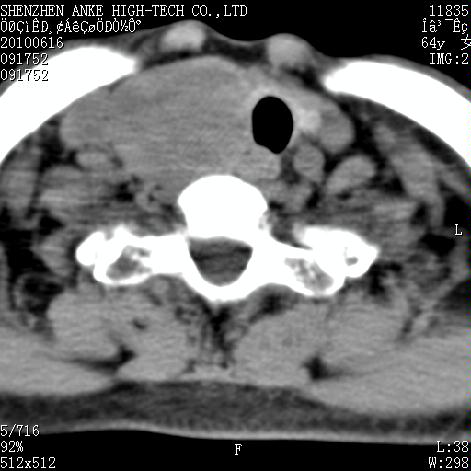

标题: CT27132:患者女,64岁,颈部及全身多处包块,现觉吞咽困难4 [打印本页]

标题: CT27132:患者女,64岁,颈部及全身多处包块,现觉吞咽困难4

右侧甲状腺占位,肿瘤可能性大,癌

右侧甲状腺癌伴右颌下腺淋巴结转移

右侧甲状腺癌伴淋巴结转移

右侧甲状腺癌伴淋巴结转移可能性大

淋巴瘤可能,再向下扫描胸部看纵隔内淋巴结

右侧甲状腺癌伴淋巴结转移可能性大。

右侧甲状腺癌伴右颌下腺淋巴结转移!建议增强!